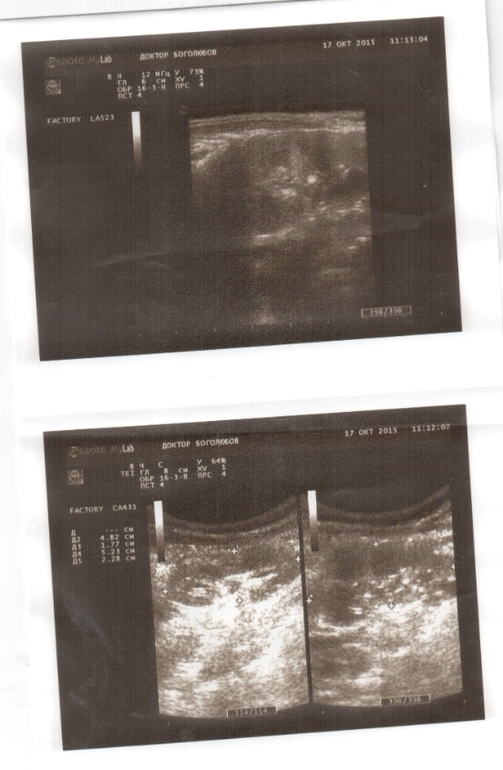

В поликлинике нам сказали, что с такими анализами нужна срочная госпитализация. Пошли мы делать узи. Узист только со второго раза смогла поставить диагноз. Говорила, что картина противоречивая.

Прилагаю все анализы и узи.

Скажите, правильно ли мы действуем? Или нам нужно срочно в стационар, как говорит педиатор? И вот эта дилатация чашечек до 9 мм. Очень меня беспокоит. Что скажете по этому поводу?